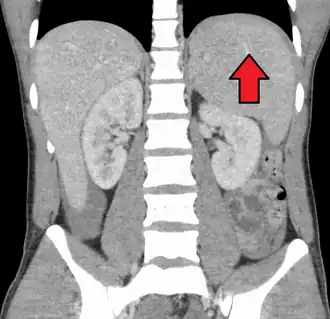

Splenomegaly due to mononucleosis resulting in a subcapsular hematoma

Spleen enlargement is common in the second and third weeks, although this may not be apparent on physical examination. Rarely, the spleen may rupture.[27] There may also be some enlargement of the liver.[25] Jaundice occurs only occasionally.[16][28]

Splenomegaly is a common symptom of infectious mononucleosis, and healthcare providers may consider using abdominal ultrasonography to get insight into the enlargement of a person's spleen.[61] However, because spleen size varies greatly, ultrasonography is not a valid technique for assessing spleen enlargement. It should not be used in typical circumstances or to make routine decisions about fitness for playing sports.[61]